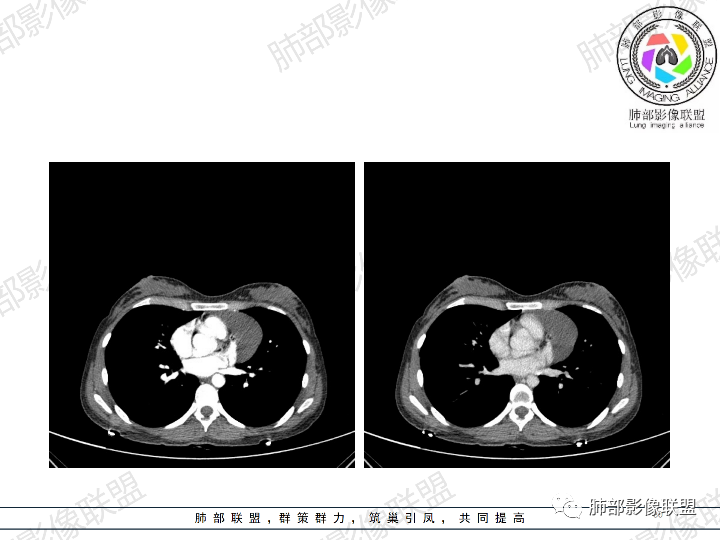

年轻女性,体检发现纵隔肿块。

影像:前纵隔一实性肿块,形态不规则,沿主动脉间隙生长,部分包绕大血管,边界欠清,周围脂肪间隙消失,平扫密度尚均匀,增强扫描大部分强化不明显,病灶左下部分似有高强化,强化病灶与血管分界清楚,考虑:1淋巴瘤(一般居中,病灶较软,包绕血管)

女性,23岁,体检发现纵隔占位。CT示前纵隔不规则占位,沿间隙生长,局部包绕大血管及心包,增强内部可见部分区域呈明显渐进性强化,其余部分强化不明显,考虑囊性畸胎瘤或神经鞘瘤>淋巴瘤,太年轻不考虑胸腺瘤

青年女性患者,体检发现左前纵隔占位性病变,胸部CT:左前纵隔见一不规则占位性病变,整体边界清楚,紧贴血管,间隙不明显,内部密度尚均匀,未见钙化及脂肪密度,增强扫描不均匀轻度强化,总体考虑偏良性病变,胸腺增生?

23岁女性

无症状

这个病灶有点怪

1、形态,似乎与常规肿瘤不一致

2、有间隔

3、密度强化有点怪

这些边缘收缩

符合胸腺正常形态

这是腺体内的一个囊性病变:

这是腺体内的另一个

倾向于:一个正常增大的腺体内的病变

根据部位:腺体首先考虑胸腺,其次才考虑异位结构

胸腺内囊、实性占位

首先支持胸腺增生并感染

其次胸腺瘤

然后才考虑异位的病变

这个病例的特点就是病灶整体符合胸腺的形态,如果它是肿瘤,它周围侵袭性不明确的话,它应该膨隆的挺厉害,它单纯就是一个膨隆性生长的,那么它就应该是类圆形的,边缘应该是膨大的,但是这个病例不是,有些地方边缘是收缩的,那么就是原有的胸腺基础上内部出了问题,里面强化增生明显就有可能是在原有胸腺基础上里面滋生出来一个病变。年龄确实年轻,又是女性。胸腺里面的病例多是胸腺瘤、胸腺癌、淋巴瘤。既然定的是胸腺里面的病变,那么就在这里面考虑。淋巴瘤首先不是。那么就是胸腺瘤和胸腺增生,胸腺囊肿的说法也有很多,因为胸腺增生里面有一种就是囊性的增生,里面有些地方有强化,囊肿合并感染了可以有,慢性炎性的肉芽肿的可以有强化。不能排除胸腺瘤,胸腺瘤放后面,一个原因就是太年轻了。如果考虑胸腺瘤,年龄不太符合,心里不踏实。我认为大家不考虑胸腺瘤是正常的思维,写报告也是待排,放第一诊断不合适。考虑有胸腺瘤是因为强化,占位效应,间隔。